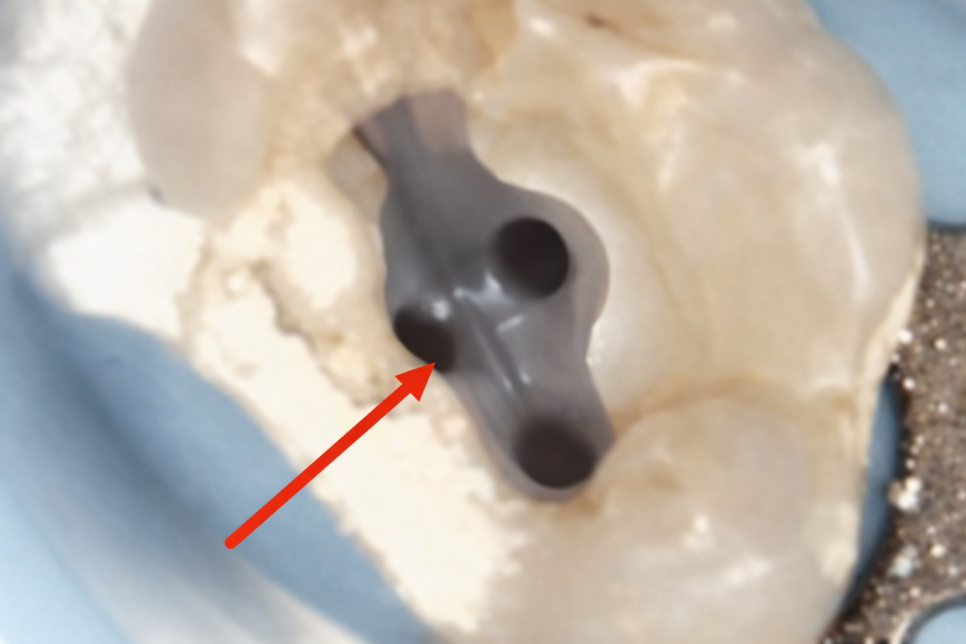

그래서 잘 보이지 않고 마곡동 치과 사진처럼

입구를 찾는 게 어려운 것이죠.

이러한 한계가 있음에도 놓치게 되면

추후 감염의 원인이 될 수 있어

이 부분까지 개선해 주는 게 좋은데요.

입구를 찾기 위해 치질을 조금씩 제거하고

분지된 신경관을 찾아냈다면,

파일로 점차 통로를 넓혀 나갑니다.